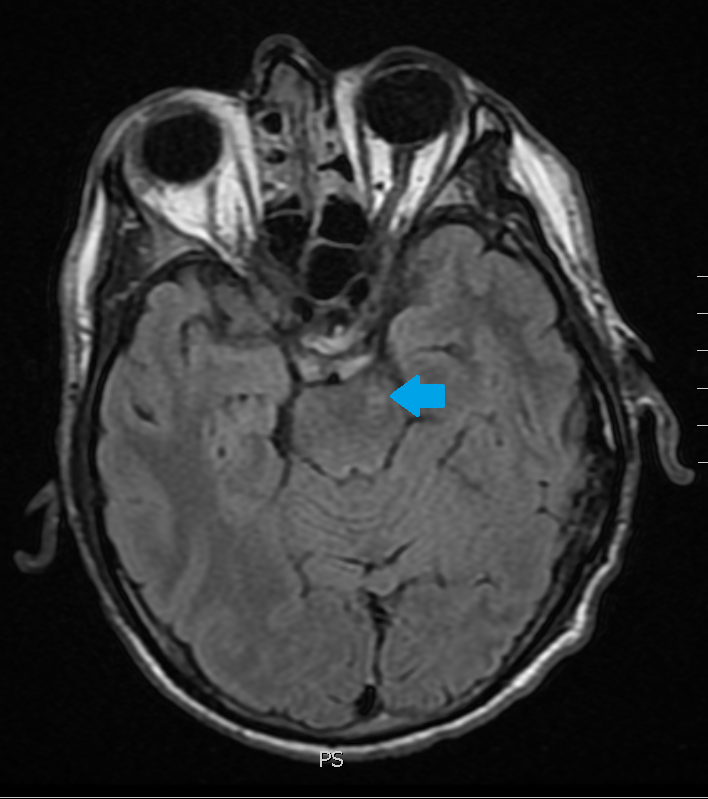

Scroll through the T2 FLAIR images in the slideshow below to follow a left basal ganglia injury with Wallerian degeneration of the descending motor axons in the brain stem.

The original injury was the small lesion on the first slide. The white matter abnormality pointed out on the subsequent slides is from Wallerian axonal degeneration.